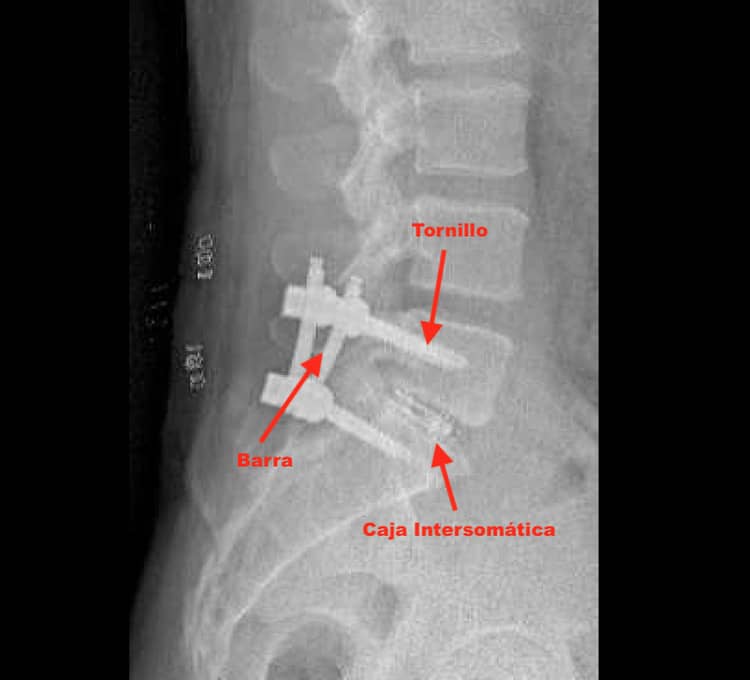

Imagen radiográfica lateral mostrando espondilolistesis L4-5 Grado II, con desplazamiento vertebral moderado visible.

La fusión vertebral es otro tratamiento quirúrgico común en pacientes con espondilolistesis. Este procedimiento consiste en unir dos o más vértebras para prevenir movimientos anormales que puedan causar dolor. La descompresión, que puede realizarse en conjunto con la fusión, se lleva a cabo para aliviar la presión sobre los nervios. Aspectos relevantes de estos procedimientos son:

- Se utilizan injertos óseos para promover la unión de las vértebras.

- El tiempo de recuperación varía, aunque podría ser más prolongado que en técnicas mínimamente invasivas.

- Es fundamental realizar una evaluación exhaustiva antes de decidir la intervención quirúrgica.